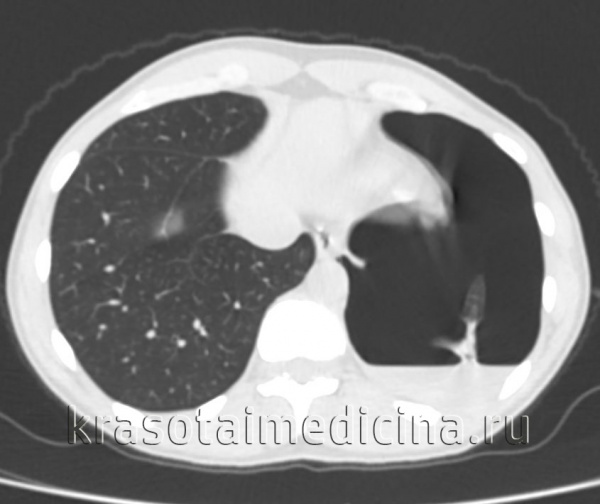

КТ органов грудной клетки. Геморрагическое содержимое в грудной полости слева, воздух в грудной полости слева, поджатое левое легкое